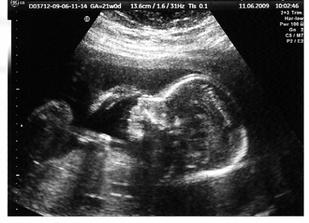

11.6.2009 Velký UTZ v Prenatalu - Tak už asi víme, co se nám v bříšku schovává :o) Ale zatím si to necháme pro sebe ... Miminko má krásnou hlavičku, obě očička, nosánek, rty, ručičky, nožičky, bijící srdíčko, žaludek, močový měchýř..... Ale je to lenoch, pořád maminku nekope...